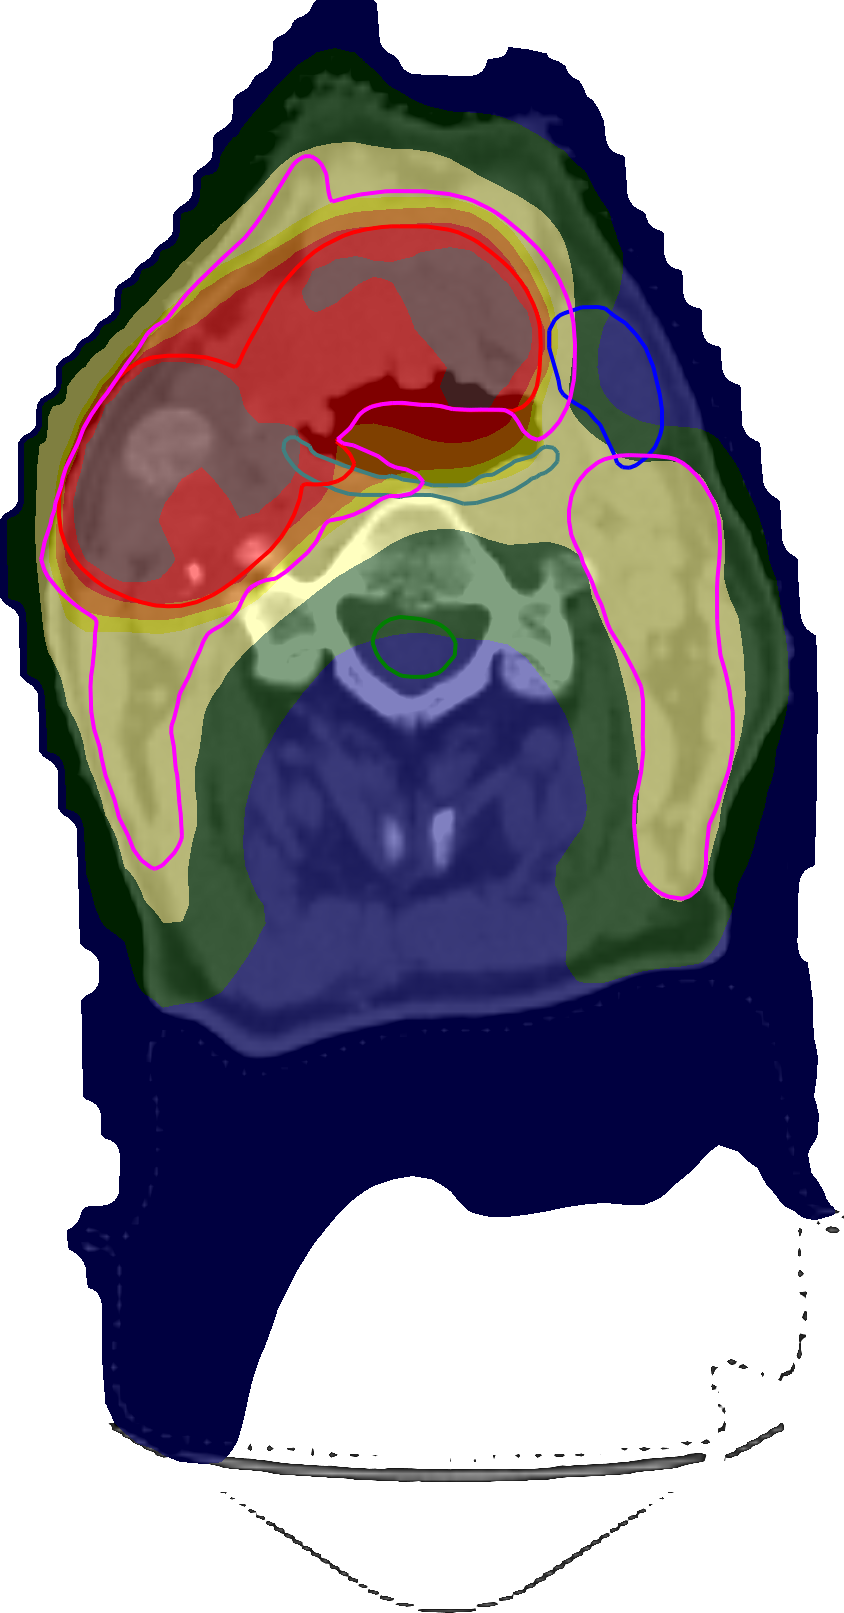

For the mostly constrained formulation, all optimizations started in the solution to the unconstrained formulation obtained from the direct optimization of clinical goals with mean-tail-dose, which was feasible with respect to all constraints. We chose the run using w~C2=105superscriptsubscript~𝑤𝐶2superscript105\widetilde{w}_{C}^{2}=10^{5}, which achieved the best overall plan quality of all values tried, to compare to the direct optimization—Table 7 shows the respective clinical goal levels after optimization and Figure 6 shows the corresponding DVHs and spatial dose distributions. While the degrees of constraint infeasibility were similar, the direct optimization was able to lower the mean dose to the middle and superior PCMs significantly better than using the conventional functions. In particular, it was observed that the optimization using the conventional formulation quickly converged while that using the direct formulation was able to steadily push the mean doses down, again showcasing the problems with vanishing gradients associated with the conventional penalty functions.

Refer to caption

(a)

(b)

(c)

Figure 6: Transversal cuts of the spatial dose distributions of the optimized plans obtained for the constrained head-and-neck test using the conventional formulation (a) and using the direct optimization of clinical goals (b). A DVH comparison between the former (dashed) and the latter (solid) is shown in (c).